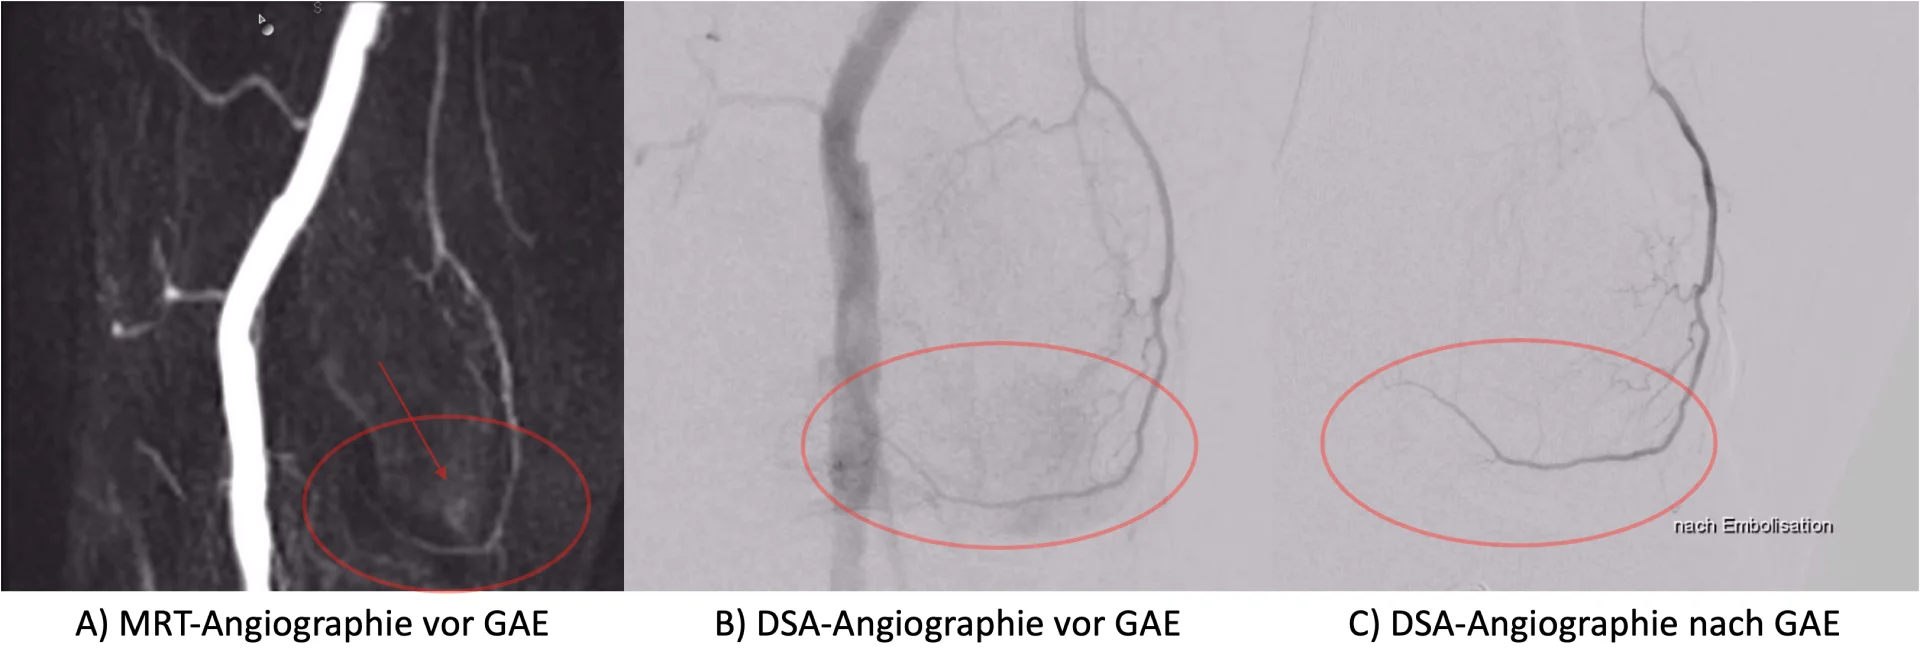

L: Gegenwärtig werden noch viele Eingriffe mittels CT durchgeführt. Das bedeutet, dass ionisierende Strahlung eingesetzt wird, die bei wiederholt hohen Dosen Schäden am Erbgut verursachen kann, welche bei der MRT-Bildgebung nicht auftreten. Ein weiterer wichtiger Punkt ist der überlegene Weichteilkontrast der MRT-Bildgebung mit welcher wir z. B. kleine Läsionen in der Leber, die im CT nicht gut sichtbar sind, wesentlich präziser identifizieren sowie gezielter biopsieren oder therapieren können. Der Wunsch nach einem zunehmenden Einsatz und zunehmender Etablierung MRT-gesteuerter Interventionen hat uns schon immer angetrieben, die Technik und die Möglichkeiten in der Radiologie weiterzuentwickeln und auszuschöpfen.

L: Besonders profitieren Patienten mit Entitäten, die eine hohe Tumorheterogenität aufweisen, unter anderem Sarkom-Patienten. Die MRT-Bildgebung hilft uns dabei, dedifferenzierte Areale zu identifizieren und gezielt zu biopsieren, da die Ergebnisse der histopathologischen Untersuchung die Therapieplanung maßgeblich beeinflussen. Dies gelingt uns z. B. durch zusätzlichen Einsatz von Techniken wie der Diffusionsbildgebung oder real-time-Radiomics–Analysen, welche dem Interventionalisten direkt während des Eingriffes zur Verfügung stehen. Ein weiteres wichtiges Einsatzgebiet ist die thermische Ablation von Desmoid-Tumoren. Hier geht es nicht nur darum, das Desmoid vollständig zu abladieren, sondern auch angrenzende kritische Strukturen wie beispielsweise Nerven und das Rückenmark zu schonen. Durch die Entwicklung von thermosensitiven Sequenzen mit unserer Forschungsgruppe am Institut für Computer Assisted Clinical Medicine (CKM) können wir in Zukunft noch präzisere Interventionen durchführen.